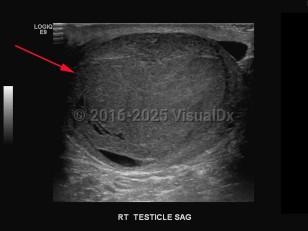

A malignant tumor of the testis (one or both), most often of germ cell origin (95%), which may be diagnosed as primary or metastatic cancer. Common presentation includes painless swelling, palpable mass or enlargement in the testis, orchidalgia, fatigue, and infertility. Other symptoms may be flank pain and dull or heavy abdominal sensation. Patients with metastatic disease, depending on the location of the metastasis, may present with gastrointestinal (GI) symptoms (nausea, vomiting, GI hemorrhage, anorexia), edema of extremities, bone pain, back pain, central nervous system abnormalities, cough, dyspnea, or neck mass. Patients with cryptorchidism have greater risk for testicular cancer.

Nonseminomatous tumors most commonly occur in patients aged 15-35, while seminomatous tumors target men a decade older. Germ cell malignancies of the testis are typically associated with a specific cytogenic irregularity (il2p). Non-germ cell tumors may arise in Leydig or Sertoli cells, or lymphomas, with non-Hodgkin lymphoma more common in men over age 60.